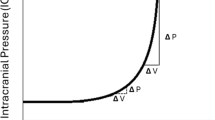

8 Effect of Hypertension on Cerebral Autoregulation

With chronic hypertension, the baroreceptor function is blunted, the autoregulatory range is higher with a rightward shift of the curve, as opposed to normotensives as shown in Fig. 17.2 [23]. Such effects are more pronounced in chronic untreated hypertensive patients, which increases the cerebral oxygen extraction fraction by up to 80%. Therefore, targeting the generally acceptable mean arterial pressure (MAP) of 65 mmHg might result in under perfusion of the brain in such patients. Hypertensives are more prone for ischemia around the periventricular white matter area since it is located at the boundary between two arterial territories such as superficial and the deep arteries. The severity of periventricular white matter injury or leukoaraiosis correlates with the magnitude of autoregulatory dysfunction [24]. The rightward shift of autoregulation indicates that they will tolerate hypertension better as compared to normotensives as presented in Fig. 17.3. However, such impaired autoregulatory response not only leads to more severe ischemia after arterial occlusion but also causes cerebral hyperperfusion during acute severe rise in blood pressure (>180 mmHg) which overwhelms the regulatory capacity disrupting the blood-brain barrier, in turn leading to cerebral edema (hypertensive encephalopathy) and intracerebral hemorrhage (ICH) [19]. Chronic untreated hypertension can cause the development of microaneurysms in small perforating arteries which are <0.9 mm in diameter, and the rupture or leak from this aneurysm could lead to ICH commonly in basal ganglia, thalamus, pons, and cerebellum. Manifestations of hypertension can be observed as end-organ damage in almost every organ system, but more profound effects of untreated hypertension are noted in cerebrovascular system, cardiovascular system, and renal system. In the brain, extraparenchymal arteries and arterioles account for 2/3 of the vascular resistance, while intracerebral arterioles and capillaries account for the remaining 1/3, therefore, vessels residing outside the brain have the greatest impact on parenchymal blood flow. Hypertension potentiates atherosclerosis which in turn potentiates constrictor responses of large cerebral arteries to serotonin and thromboxane contributing to vasospasm and transient ischemic attacks.